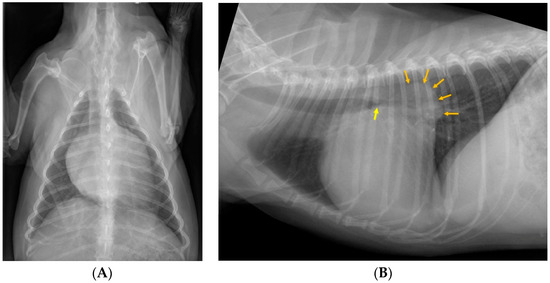

3.3. Image Review

3.4. Sensitivity and Specificity of Bronchial Compression/Collapse as a Predictor of Cough

3.5. Correlation of Radiographic Variables with Chronic Cough